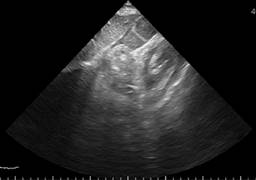

A transthoracic echocardiogram was performed that showed septoapical, apical, inferior apical akinesia, no thinned cardiac segments. Left ventricular ejection fraction (LVEF) 45%, type 1 diastolic dysfunction E/A 0.6, E/e 10, normal dimensions of the right heart chambers with normal right ventricular ejection fraction at rest. Systolic pulmonary artery pressure 26 mmHg, estimated by tricuspid reverse gradient. No pericardial effusion at rest (Figures 1 to 3). The patient evolved to be hemodynamically stable, so a stress echocardiogram was performed to search for viability/residual ischemia on the 6th day after admission to hospitalization. A 5-stage protocol was initiated, starting at 5 μg/kg/min, reaching 20 μg/kg/min. The patient persisted with septoapical and apical akinesia and developed an ischemic response due to developing basal and medial inferior hypokinesia. No changes were recorded in the electrocardiogram at this dose of dobutamine. Esmolol 30 mg intravenous single dose was administered at the beginning of the recovery phase and the study was terminated. In first minutes of recovery, the patient showed sudden deterioration in alertness and pulseless electrical activity. The echocardiogram showed pericardial effusion with a hematic appearance and echocardiographic data of tamponade (Figures 4 to 6). The patient presented cardiorespiratory arrest, so intravenous fluids were administered and an emergency pericardiocentesis was performed, achieving expansion of the right ventricle but with rapid formation of a new pericardial effusion. Later on, he presented asystole which did not revert to basic or advanced cardiovascular resuscitation.